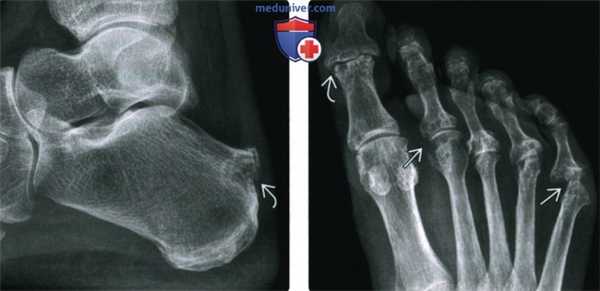

(Слева) Рентгенография в ПЗ проекции: визуализируется мягкотканное образование, разделяющее 1-й и 2-й плюснефаланговые суставы. У этой женщины 45 лет образование характеризовалось болевым синдромом. У основания проксимальной фаланги 1-го пальца визуализируется совсем маленькая краевая эрозия. Этот признак, наряду с возрастом и полом позволяет заподозрить РА, однако требуется дополнительная оценка.

(Справа) МРТ, сагиттальная проекция, режим Т1. опухолевидное образование у этой же пациентки, скорее не имеющее выраженных особенностей и характеризующееся среднеинтенсивным сигналом. Участок 1-й плюсневой кости, представленный на срезе характерных особенностей не имеет. (Слева) МРТ, короткоосевая аксиальная проекция, Т2 с подавлением сигнала от жира: отек костного мозга головки 1-й плюсневой кости (эта же пациентка). Суставной выпот в 1-м плюснефаланговом суставе смещает сухожилие разгибателя. Между 1-й и 2-й плюсневыми костями визуализируется опухолевидное образование В со смешанным сигналом.

(Справа) МРТ, короткоосевая аксиальная проекция, Т1 с контрастным усилением и подавлением сигнала от жира : визуализируется накапливающая контраст синовиальная оболочка, ограничивающая выпот в 1-м плюснефаланговом суставе В. Образование представляет собой жидкость с сигналом низкой интенсивности и толстым контрастируемым ободком. По совокупности факторов - это межплюсневый бурсит.

(Слева) Рентгенография в ПЗ проекции: остеопения в зоне 4-го и 5-го плюснефаланговых суставов с размытостью кортикального слоя головки 4-й плюсневой кости. Истинные эрозии и субхондральные кисты визуализируются в области головки 5-й плюсневой кости, которая является зоной наиболее частого поражения на стопе при РА. МРТ позволяет более подробно визуализировать признаки патологических изменений.

(Справа) Несмотря на отсутствие эрозии в зоне 4-го плюснефалангового сустава, в области головки 4-й плюсневой кости визуализируются ранние признаки РА в виде отека и выпота.